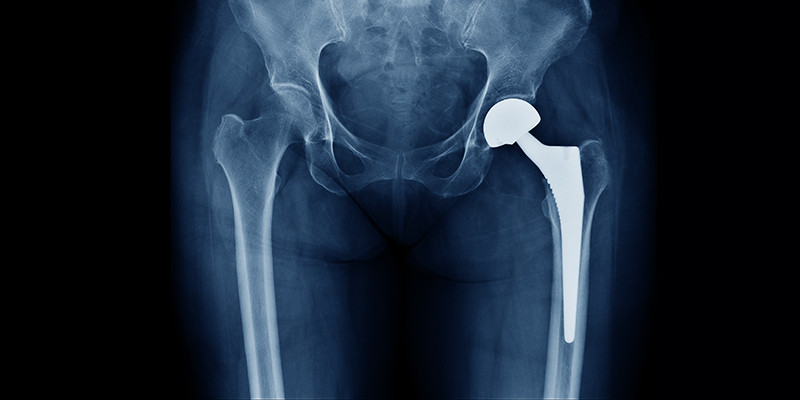

Hoelang gaat een heupprothese mee?

Het eindstadium van coxartrose leidt vaak tot een heupprothese. Een operatie is over het algemeen effectief. Dit onderzoek laat zien, voornamelijk op basis van nationale registraties, dat 58% van de heupprotheses na 25 jaar nog in situ is.